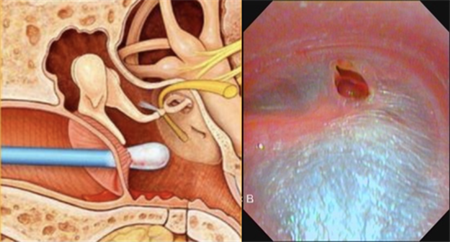

但不是让我们自己掏,而是要去医院耳鼻喉科请医生做专业的诊断,再用专业的器材小心地取出来,必要时还需要配合其它治疗。

不是自己捣鼓一下,或者找采耳师傅就能解决得好的。

耳道里的皮肤是很敏感、很脆弱的,一不小心就容易擦伤耳道壁、损伤鼓膜、戳伤鼓膜造成穿孔。

关系到脆弱的耳朵,永远不要对自己的手法太过自信。来硬的不行,那软的可以吗?比如,只是拿棉签或硅胶耳勺?

当然也是不建议的,因为很可能将耳屎(尤其是油性耳屎)推向更深处,造成或者加重耳垢栓塞。